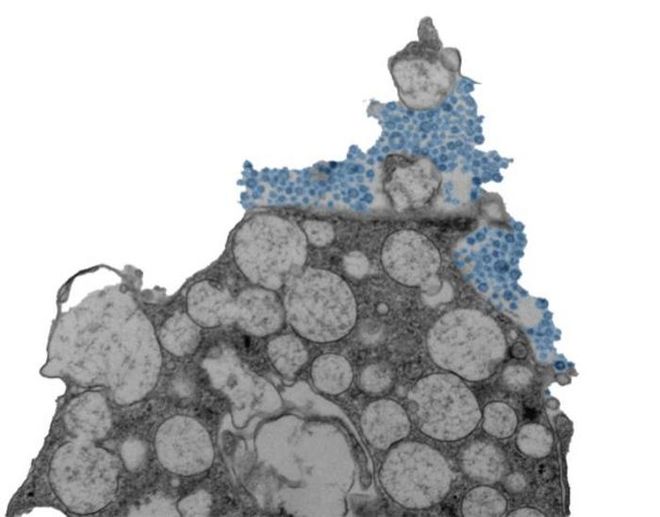

Image of the human nasal epithelial cell releasing rhinovirus, which is in blue.

(Image Credit: Lysenko Andrii/CC BY-SA)